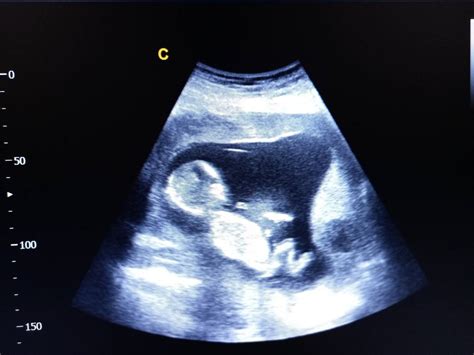

Săptămâna 6 este marcată de ecografia de confirmare, unde vei putea auzi, probabil, pentru prima dată inima bebelușului. Embrionul are un aspect curbat, cu mici umflături pentru brațe și picioare, și muguri pentru ochi și urechi. Pot apărea primele simptome de sarcină, precum sensibilitatea la mirosuri sau sâni mai plini.

Pavilioanele urechilor și structura internă încep să se formeze. Chipul bebelușului permite distingerea buzei superioare și a două nări minuscule. Maxilarul și mandibula cresc, conținând viitorii dinți de lapte. Inima este complet formată și bate cu o frecvență de 180 bătăi/minut. Bebelușul începe să facă mișcări bruște, vizibile ecografic. Se recomandă dublul test pentru evaluarea riscului de anomalii cromozomiale și vaccinarea antigripală.